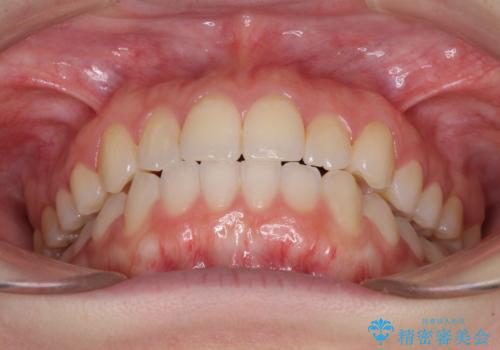

前歯のクロスバイトをインビザライン矯正で改善

上の前歯が下の前歯を乗り越える際、奥歯がほとんど咬めない時期があり、乗り越えた後も、インビザライン特有の奥歯の咬みにくさが続きました。

咬み合わせ改善のために治療期間を要しましたが、最終的に奥歯はしっかりと咬めるようになりました。